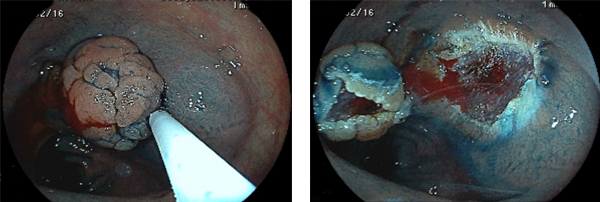

サイズの大きいLST(側方発育型腫瘍:低異形度腺腫)のEMR例

右:スネア(輪っか)を病変全体が入るようにかけてゆっくりと縛ります

右:病変が切除されました 一部に出血が見られます

右:縫縮が完了(創が治癒するとクリップは自然に脱落し、便と共に排出されます)